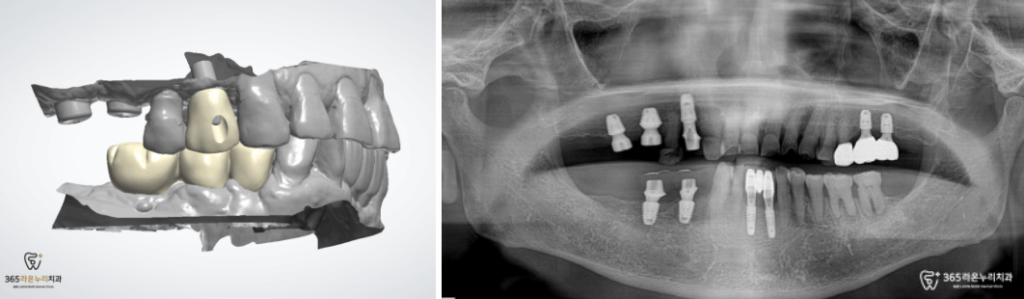

2개월이 지난 이후 보철을 연결할 수 있도록

어버트먼트와 같이 임시 치아를

제작해드리기로 합니다.

그 사이, 왼쪽 위턱의 최종 크라운을

제작하기 위해 스캔본을 뜨고

정교하게 제작된 크라운을

올려 완성해드릴 수 있었습니다.

이어서 파절되어 있었던 왼쪽 작은 어금니

코어 및 크라운도 진행해드렸습니다.

그렇게 유착되기를 기다리면서

오른쪽 위 아래 모두 어버트먼트+임시 치아를

올려드린 모습입니다.

그이후, 아래턱에 최종 크라운을

올려 튼튼한 치아를 완성했습니다.

시간이 흘러, 오른쪽 위턱의 어금니부위도

잘 완성되어 최종 크라운까지 올려드릴 수 있었습니다. ^^